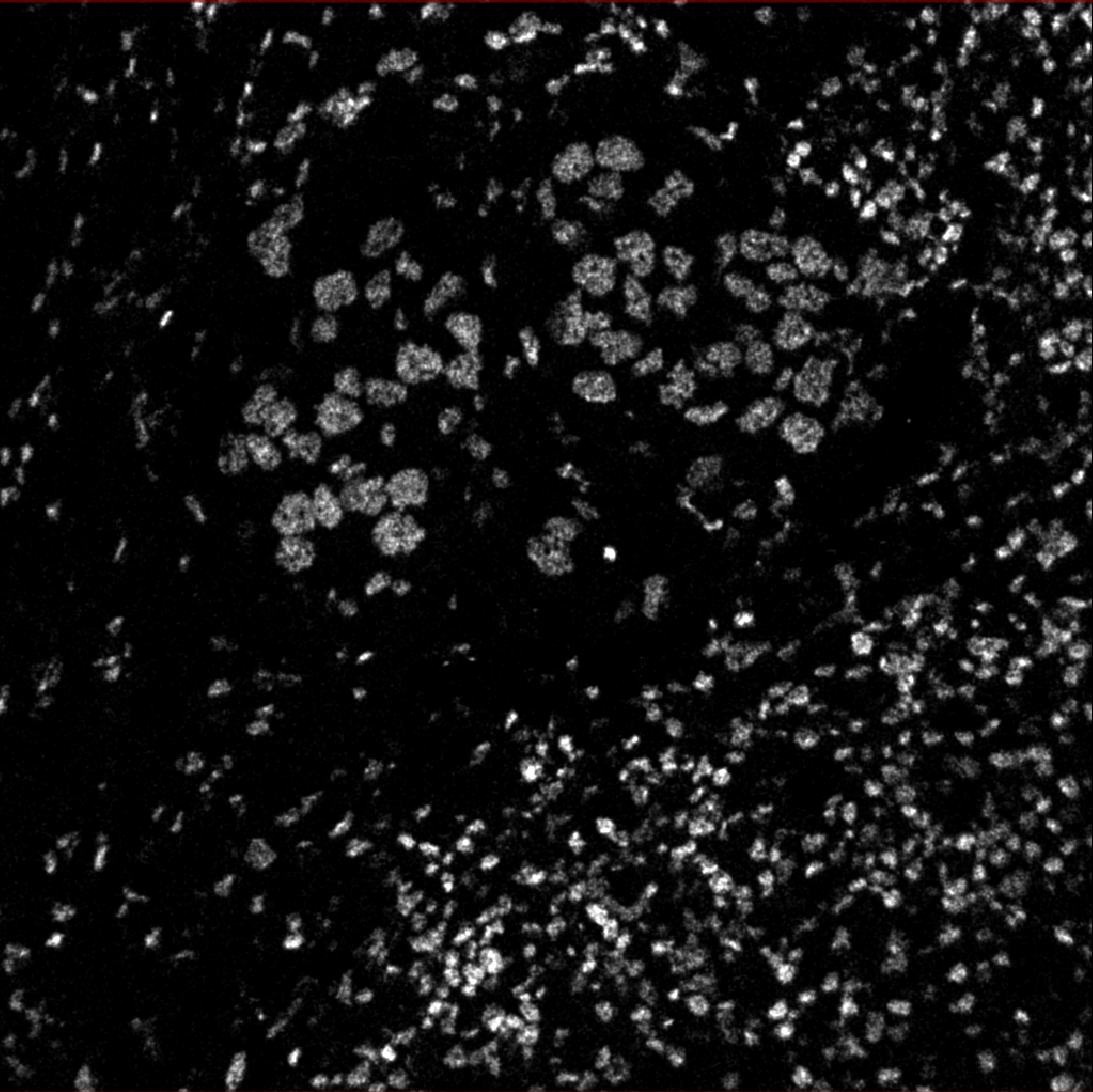

The below images were generated with that notebook run locally over this sample data: HuggingFace. The data includes lots of 1024x1024 cell images.

The notebook preprocesses input channels into an image file that’s sent to DeepCell.

Then DeepCell predicts cell segmentation and sends data back, processed into an image overlay.